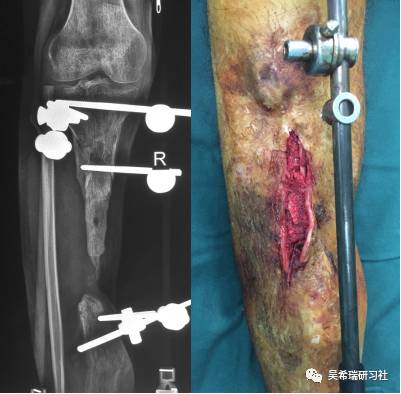

病例4

车祸伤多发伤胫骨近端开放骨折软组织缺损右上肢截肢

TIPS:开放骨折外固定游离植皮缩小伤口搬移+半开放植骨半开放植骨=骨水泥技术+开放植骨+骨搬移横向、前后调整搬移骨块下地走路刺激骨愈合早期关节功能锻炼